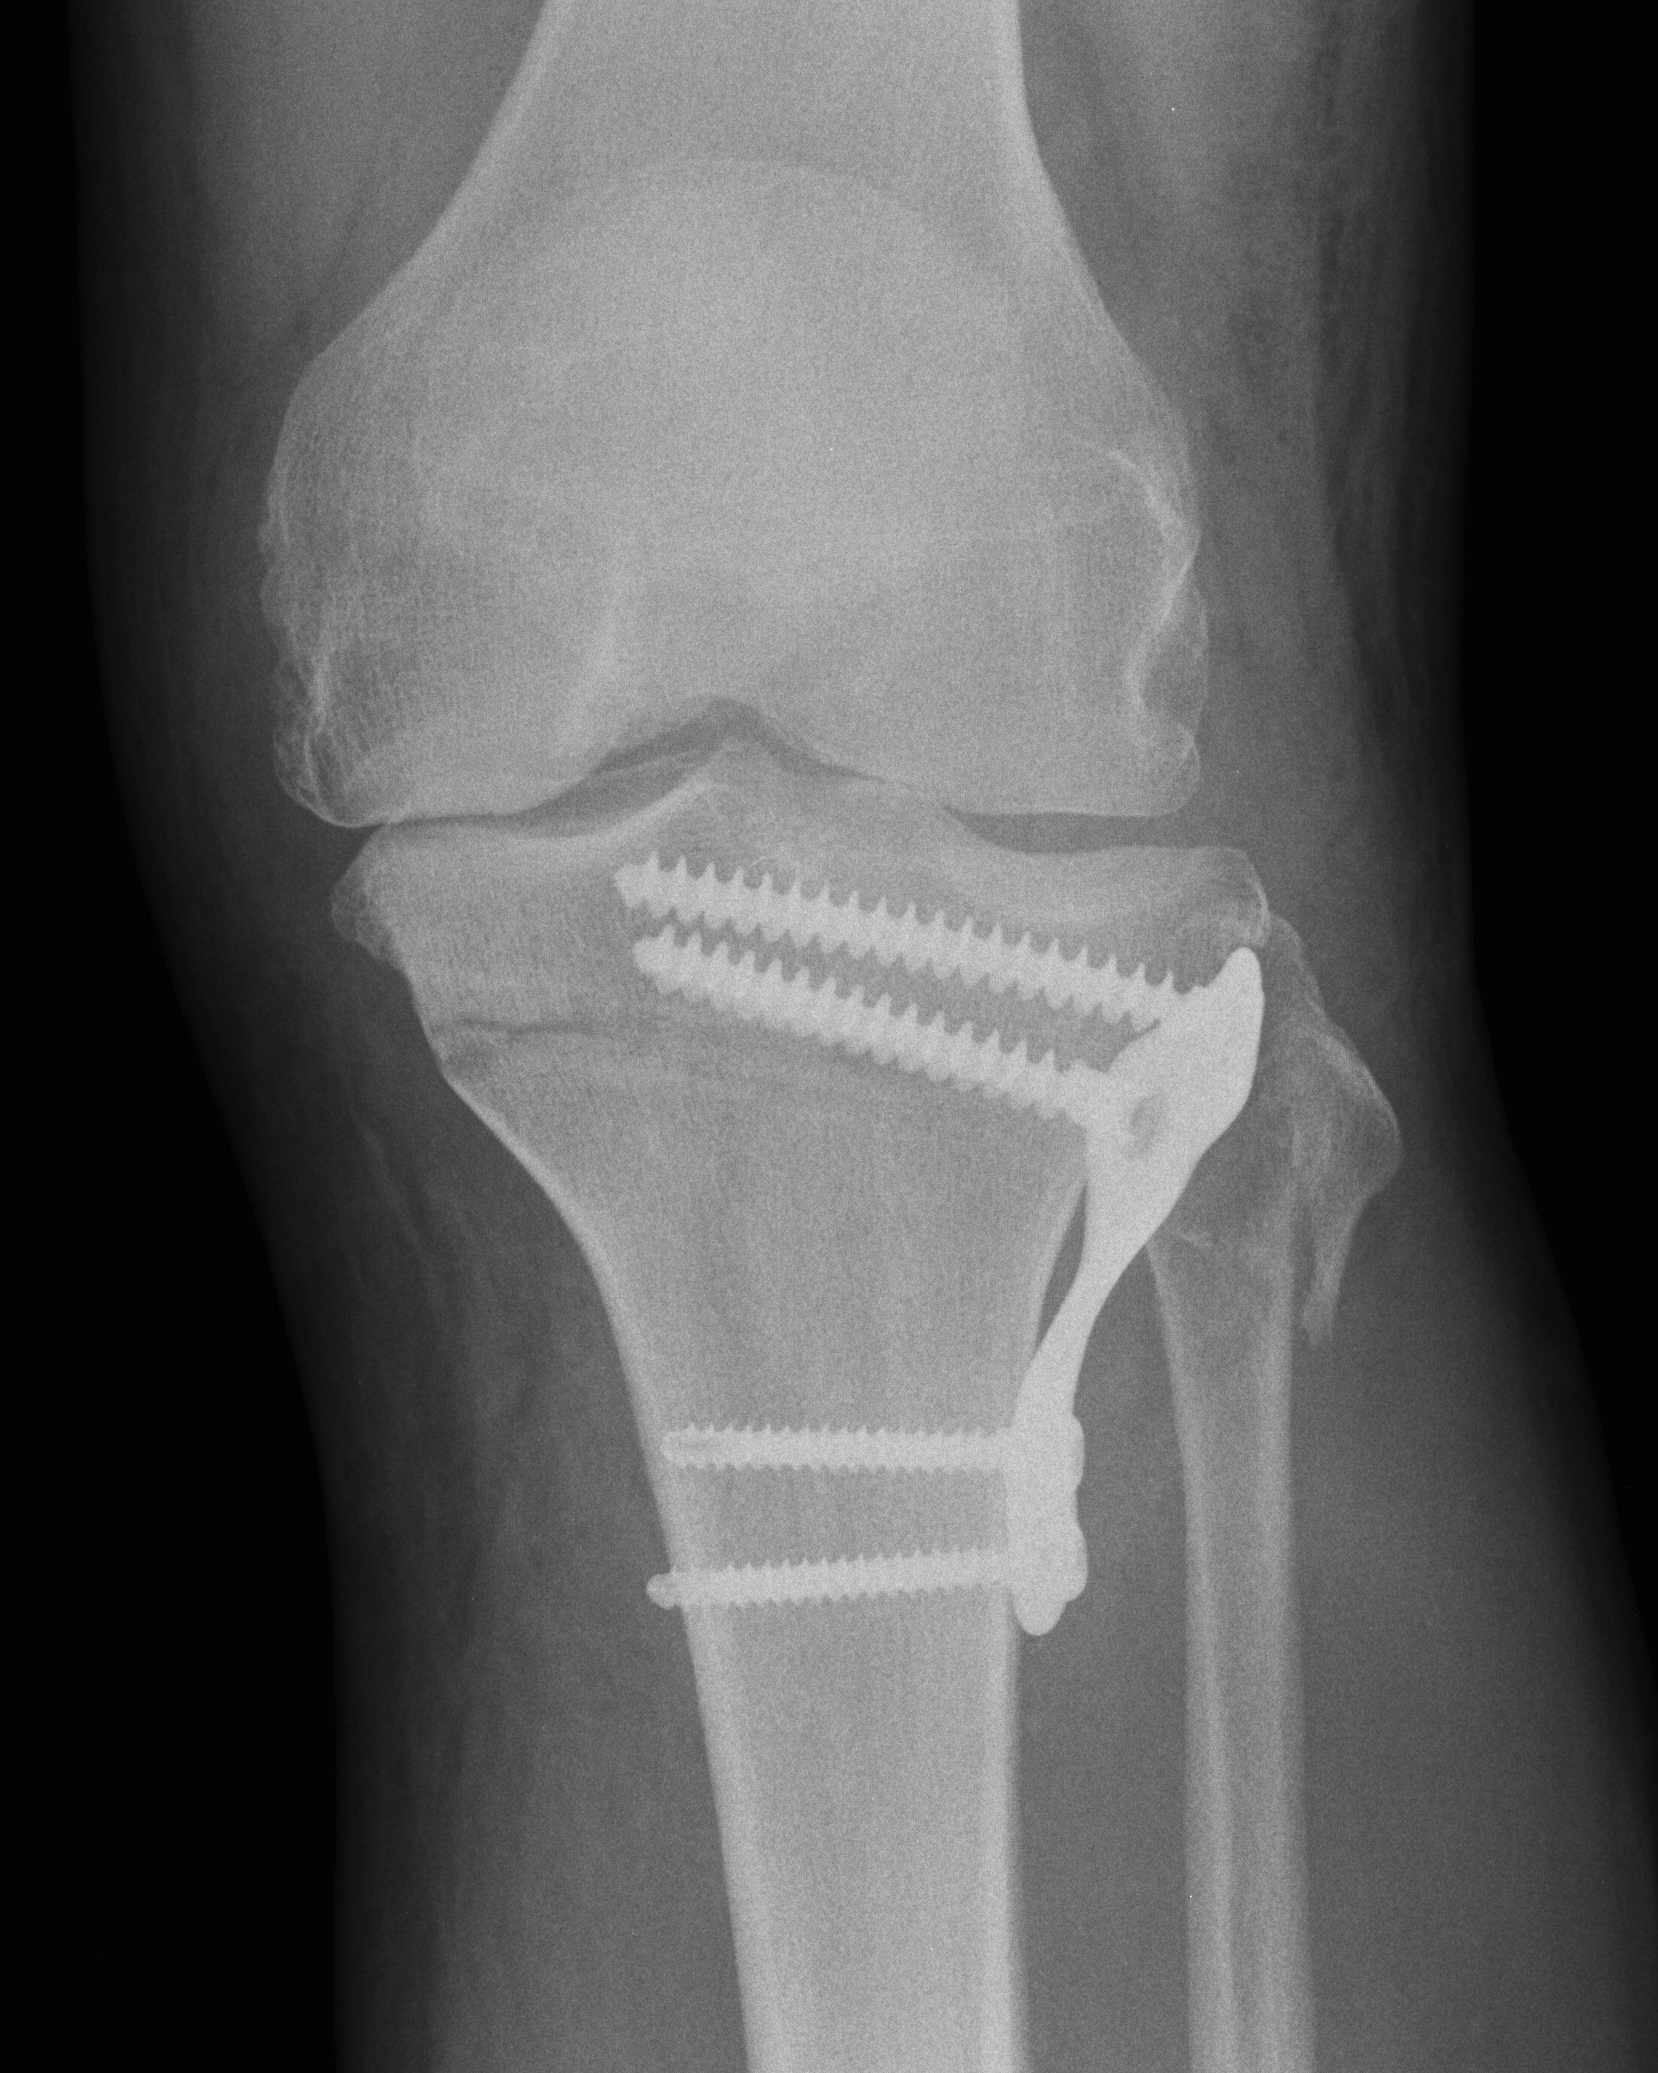

Difference between closed wedge high tibial osteotomy CWHTO a b best sale, High tibia osteotomy. a with closing wedge b with opening best sale, A closing wedge proximal tibial osteotomy. Download Scientific best sale, Knee Osteotomy Saint Luke s Health System best sale, Technique Closing Wedge The Bone School best sale, Medial closing wedge high tibial osteotomy for valgus tibial best sale, Technique Closing Wedge The Bone School best sale, Truffle Collection wide fit closed toe wedges in black ASOS best sale, Buy Women s Closed Toe Wedges Famous Footwear Australia best sale, Lateral Closing Wedge Osteotomy Musculoskeletal Key best sale, ASOS DESIGN Wide Fit Tyra closed toe wedges in natural linen ASOS best sale, Soda Black Closed Toe Wedge Heels Black heels wedges Black best sale, Closed Toe Wedge Sandals Tan Women s Shoes Monsoon Global best sale, Hitomi espadrille woven closed toe 8cm wedge heel sandals denim blue best sale, Vionic Anna Closed Toe Wedge Sandal Free Shipping Returns best sale, Tommy Hilfiger BASIC CLOSED TOE MID WEDGE Black Fast delivery best sale, Full Closed Wedge Heel Black best sale, Closed Toe Wedge Sandals Tan Women s Shoes Monsoon Global best sale, Lateral Closing Wedge Osteotomy Musculoskeletal Key best sale, Wedge Sandals Black Closed Toe Stiletto Heel PU Leather Black best sale, TUOBARR Wedge Platform Sandals Women s Closed Toe Buckle Strap best sale, ASOS DESIGN Wide Fit Treasure closed toe wedges in natural fabric best sale, Closed toe Slingback Wedge 10609 Aerosoft best sale, Madison Cleo Closed Toe Espadrille Wedge Navy Madison Heart of best sale, Wedges Sandals Shoes High Heel Hessian Cushioned Ladies Closed Toe best sale, Amazon mysoft Women s Wedge Pumps Closed Toe Low Heel Dress best sale, Cranial Tibial closing Wedge Osteotomy CTWO with patient specific surgical guides best sale, Women s Espadrille Wedge Heels Closed Toe Ankle Strap Temu best sale, Comparison between conventional and hybrid closed wedge high best sale, WHITE WEDGE HEELS Leather Heels Ankle wrap Sandals White best sale, Amazon Ruanyu Womens Platform Espadrilles Wedge Sandals Slip best sale, Froggie 10572 Closed Wedge in French Featherbys best sale, Closed Toe Wedge Sandals Tan Women s Shoes Monsoon Global best sale, Closed toe wedge sandal in beige lace by Refresh Isabel s Retro best sale, Closed Wedge Socket De Haan Special Equipment best sale, amlbb Womens Wedge Sandals Closed Toe Wedges Shoes Platform best sale, Wonders Closed Toe Wedge Sandals Silver 6703 The Shoe Horn best sale, Talitha closed Black Wedge Charming Shoes South Africa best sale, Closed Toe Wedges Shop Closed Toe Wedges Macy s best sale, Closed Toe Wedges Etsy best sale, Closed toe Slingback Wedge 10609 Aerosoft best sale, Heels Rumor Closed Toe Wedges Dorothy Perkins best sale, Franco Rossi Allison Closed Back Wedge Black Shoe Box Online best sale, Closed Wedge Sockets CWS RopeBlock best sale, Westlyn Closed Toe Wedge Sustainable Shoes Reformation best sale, Office High Heel Wedge Pumps Closed Toe Slip on Shoes for Work best sale, Lateral femoral closing wedge osteotomy in genu varum ScienceDirect best sale, Sensational Black Closed wedge Order from Rikeys faster and cheaper best sale, Lace Up Ankle Closed Toe Jute Trim Wedges Closed toe espadrilles best sale, Tibial Osteotomy with Closed Wedge best sale.

Lateral Closing Wedge Osteotomy Musculoskeletal Key